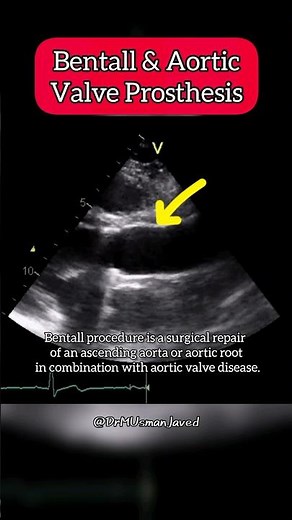

Bentall and aortic Valve Prosthesis on Echocardiography #aortic #Heart

已浏览 8069 次

2024年8月9日

YouTube

Dr. M Usman Javed

Bentall and aortic Valve Prosthesis on Echocardiog

…